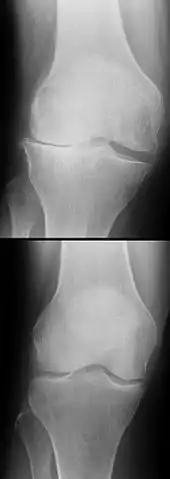

Procédés d'imagerie

Le diagnostic peut être confirmé par imagerie (IRM). Mais il faut noter que l'interprétation de l'IRM seule pour le diagnostic de rupture de LC conduit à 20 % de faux diagnostics. Cela dépend des images de coupe et de la position appropriée du genou pendant l'IRM. Le radiologue doit connaître avec précision les circonstances qui ont conduit à la blessure, et avoir aussi une bonne expérience de l'étude d'une articulation blessée, pour éviter les faux diagnostics. Pour comparer avec l'IRM, le taux d'erreur du test de Lachman, bien plus simple à accomplir, n'est que de 10 %[104],[105],[106],[107]. L'IRM est donc généralement moins sensible et moins spécifique que l'examen clinique par un orthopédiste qualifié[108]. Le résultat de l'IRM n'a que relativement rarement une influence sur la formulation finale du diagnostic[109] et ne devrait pas servir de remplacement pour une anamnèse soigneuse et la palpation[15]. Plusieurs études arrivent à la conclusion que l'IRM n'a de sens que pour des blessures complexes difficiles à expliquer, et là, pour éviter de poser un diagnostic négatif[110],[111],[112].

Les radios n'apportent aucune contribution immédiate au diagnostic de rupture de LC. Les deux LC sont invisibles à la radio, déchirés ou non. La seule utilité de la radio ne peut servir qu'au diagnostic des complications osseuses possibles.